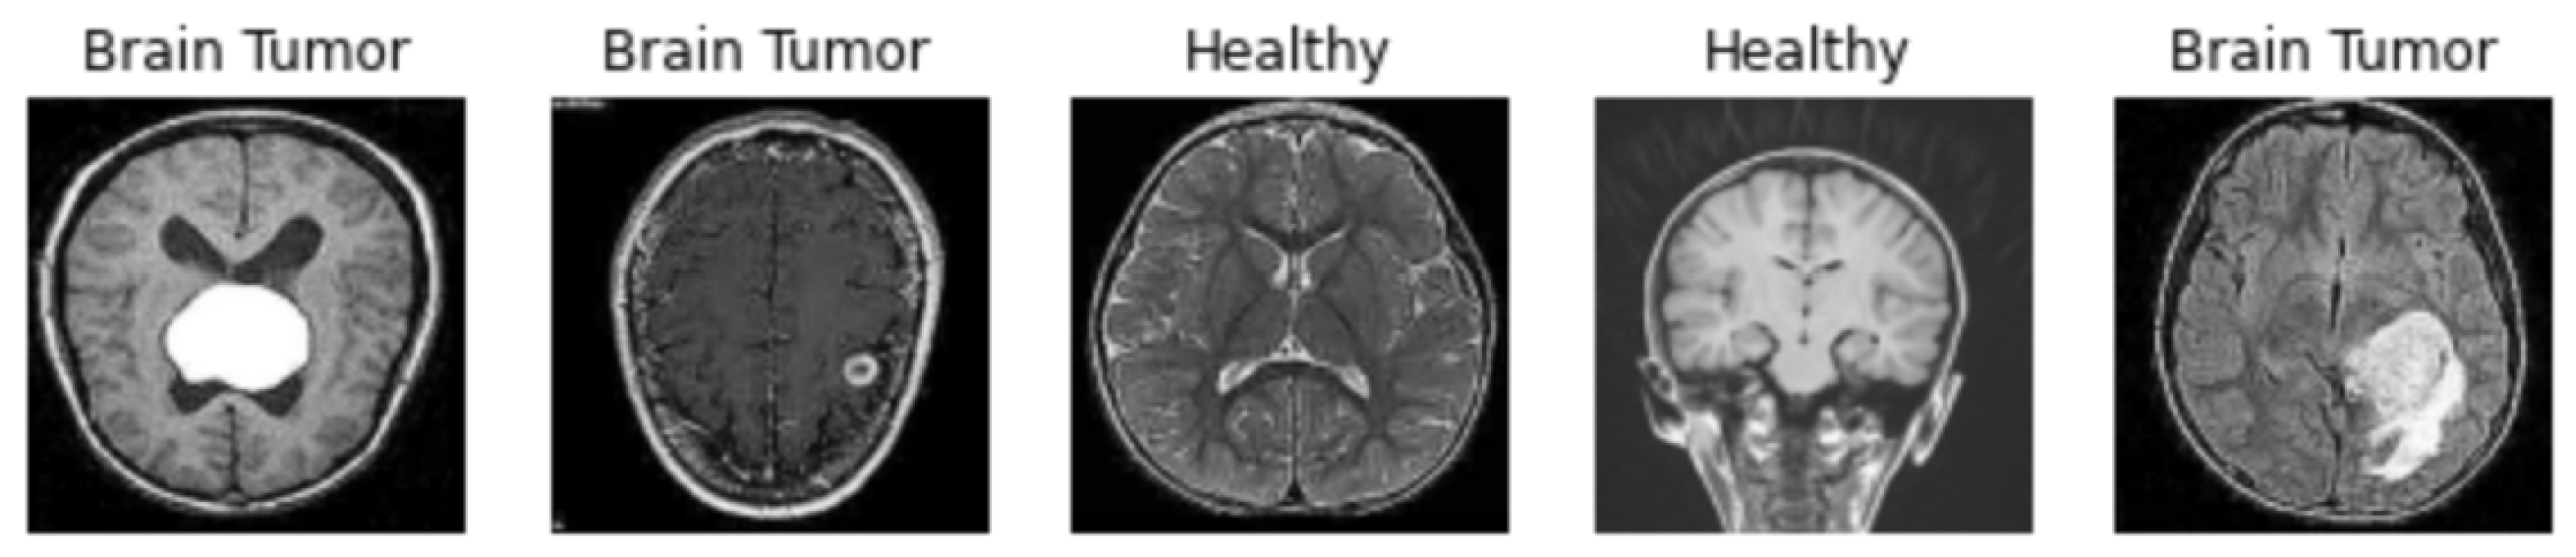

1.1. Related Work

3. Results of Experiments and Discussion

3.3. Results Obtained by the CAM and Grad-CAM Methods